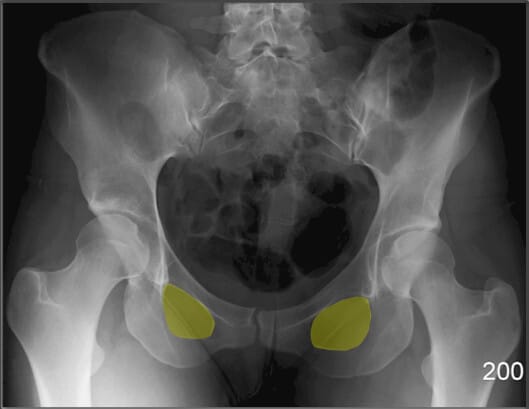

좌골결절 (Ischial Tuberosity)

| 좌골결절 (Ischial Tuberosity) |

| ✅ ‘앉는 뼈’라고도 불리는 부위로, 체중이 걸리는 지점입니다. AP pelvis 영상에서 골반의 가장 하단에 큰 음영으로 보입니다. |

| 🔴 햄스트링 기시부위로 근육 손상 및 견열골절이 발생할 수 있는 부위입니다. |